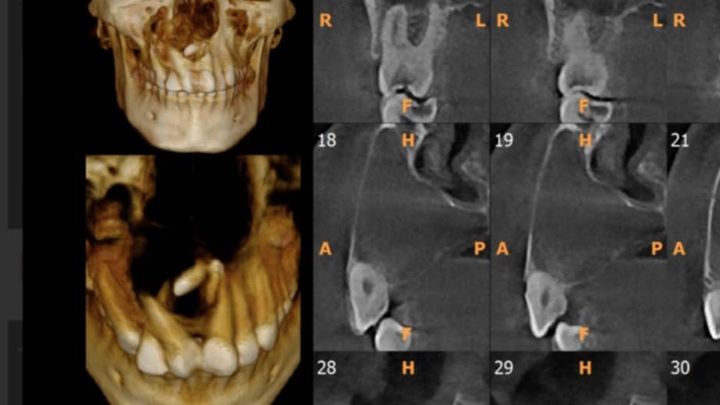

Hola queríamos pedirles un poco de apoyo para Isai Tiene un quiste maxilar y esta dañando su hueso y ya creció hacia sus senos nasales y tiene dientes numerarios que le se le tienen que operarlo y sale en $4,500 si nos pueden ayudar si lo agradecería mucho y si no nomás comparte lo porfavor